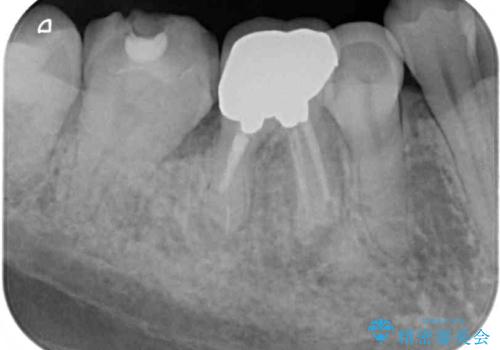

奥歯は歯根周辺の歯槽骨が広範囲に失われており、抜歯が必要と判断されました。

根管治療を行ったは、以前の治療で開けられて思われる穴が歯の内部に開けられており、炎症を起こしていました。

根管治療と合わせて、穴の開けられている部分を修復したところ、炎症による歯槽骨吸収に改善が見られました。

インプラント埋入にあたり、歯槽骨での炎症が広範囲であったことから、事前に骨造成を行いました。

歯槽骨の高さや幅を回復することができ、望ましい位置にインプラントを埋入することができました。